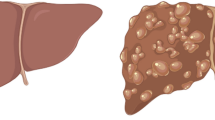

The vessel trees and the lesions are clearly visible under US scanning. Figure 9 compares hyperechoic, anechoic, and hypoechoic real lesions to the three respective masses in the phantom.

Anechoic, Hyperechoic, Hypoechoic lesions. In the first column are displayed the phantom lesions while, in the second, three examples of real masses. The picture in the first row represents the anechoic mass which is totally ascribable to a cyst, confirmed comparing it to the picture of a real mass in the upper right corner (first row, second column). Similarly, proceeding by rows, the second picture to the left is attributable to the angioma (right) and in the last row the hypoechoic lesion in the phantom simulates optimally a real HCC—Hepato Cellular Carcinoma—(right)